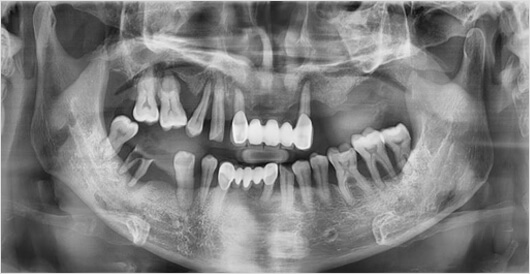

임플란트의 기둥역할을 하는 어버브먼트는

치아, 잇몸의 모양과 비슷한 것이 좋습니다.

1. 높은 장기 안정성

2. 교합력 분배로 보철물 파절 방지

3. 보철물 회전이나 탈락 방지

4. 자연치와 가장 비슷한 저작력 회복

5. 심미적인 임플란트 결과